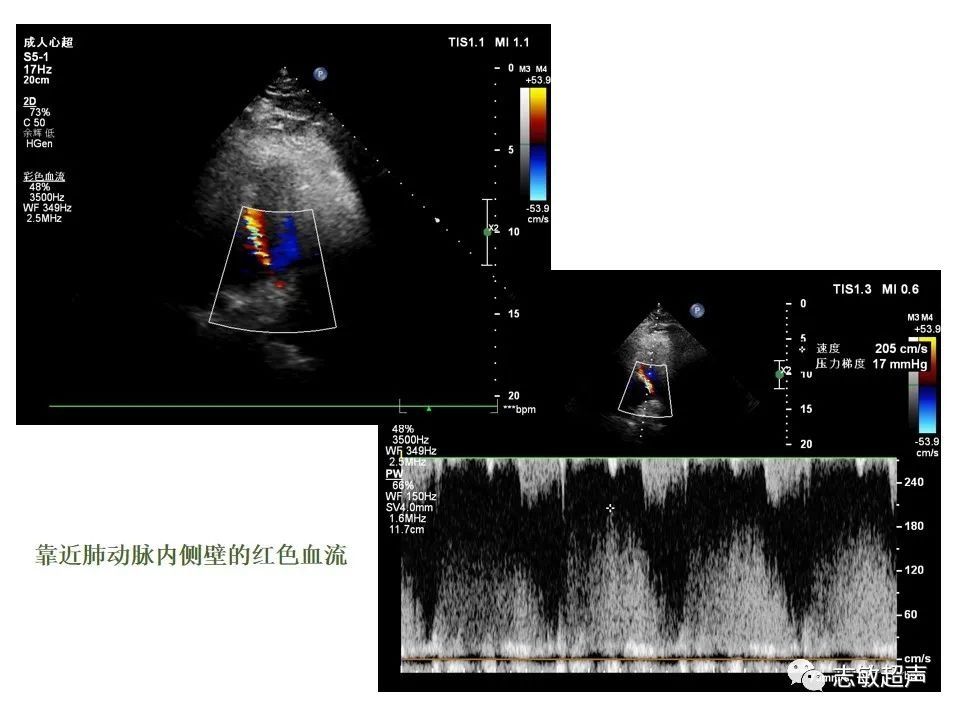

4.冠状动脉肺动脉瘘

冠状动脉-肺动脉瘘视频